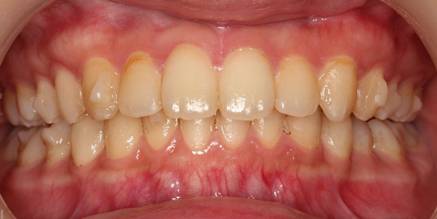

インビザGOによる矯正症例1 16歳男性

マウスピース矯正開始前。右上犬歯が内側にありました

前から見たところ

4か月後。犬歯が外側に出てきました

治療終了後10か月